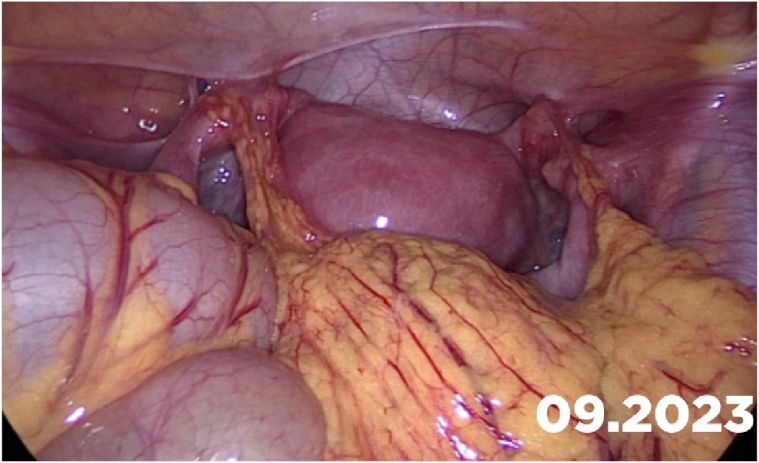

Case: A two-year-old girl presented with a mass protruding through the introitus diagnosed with vaginal ERMS and treated with chemotherapy (CHT) alone due to complete response. Six months after the last CHT dose, because of the development of local recurrence, second-line CHT was initiated and the patient was referred to our institution for a local treatment plan. Following three cycles of CHT, intracavitary VBT was administered at different time periods with a total dose of 36 Gy. Six weeks after completion of VBT, vaginoscopy was performed with no evidence of residual disease and a nonlatex 22 French foley catheter placed in the vagina (Figure 2). The patient continued to receive CHT for about six month. With follow-up vaginoscopy performed every 3 months, the stent was replaced in the same fashion and remained in place for a total of 6 months. Since vaginal stenosis was detected 3 months after the stent was removed (Figure 3), the stent was placed again and remained in place for another 6 months. The patient did not develop any stent-related complaints. After 18 months of follow-up, control vaginoscopy revealed normal vaginal mucosa with no lesions or erosions.

Figure 2.

A nonlatex 22 French foley catheter placed in the vagina.

Figure 3.

Placement of the stent after 3 months.